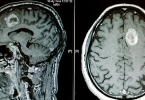

4、淋巴瘤:病毒感染可能导致淋巴瘤的发生,病毒在体内的扩散和繁殖会刺激肿瘤生长,进而影响白细胞水平。手术切除肿瘤是常见的治疗方法,术后可能需要配合化疗或放疗。